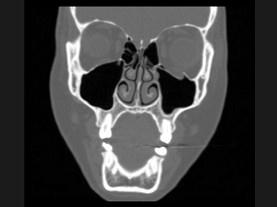

问题 25岁女性,车祸伤及面部,X线及CT检查如图所示,下列哪些描述或诊断正确 ( )

选项 A、考虑为左侧眶底骨折 B、左侧上颌窦积液 C、CT发现左侧眶底骨质断裂 D、左侧上颌窦内见气-液面 E、X线示左侧眶底较正常变低

答案 ABCDE